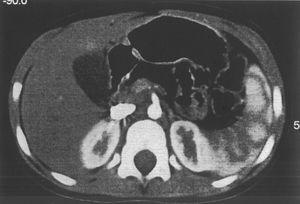

Se le realiza un hemograma y bioquímica básica en la que se objetiva una fórmula leucocitaria con linfocitosis y neutropenia (730/μl), así como una GOT de 110 y una GPT de 124, siendo el resto de parámetros normales. Se descarta hepatopatía por virus hepatotropos más habituales, déficit de a1-antitripsina, enfermedad de Wilson, fibrosis quística, trastornos metabólicos más frecuentes, patología hepática autoinmune, miopatía oculta y enfermedad celíaca. Se solicita una ecografía abdominal (fig. 1) en la que se observa una hepatomegalia homogénea y un aumento de ecogenicidad en páncreas. Ante la sospecha de SDS se solicita una elastasa pancreática: 52 μg/g de heces (insuficiencia grave 6,7), una serie ósea que se informa como normal y una tomografía computarizada abdominal (fig. 2) donde se objetiva una disminución difusa y homogénea de la atenuación del páncreas, que muestra un tamaño en los límites bajos de la normalidad; los hallazgos se relacionan con una infiltración grasa global de la glándula.

Figura 1. Aumento de ecogenicidad pancreática.